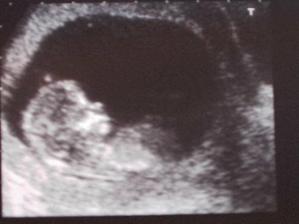

5.10. - ultrazvukové vyšetření NT+ na vývojové vady dopadlo dobře!!

26.10. -kontrola dopadla dobře, miminko odpovídalo 15+2 tt, snad už se příště dozvím co to čekáme🙂